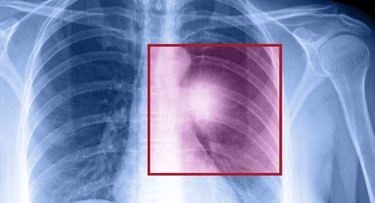

Doktorunuz göğüs boşluğundaki organların ve yapıların durumunu gösteren görüntülerde kalp yetmezliği, kanser, zatürree, pulmoner ödem gibi bir duruma dair ipuçları arar. Örneğin, akciğer dokusunda görülen yoğunluk artışı kitle ve nodüle işaret edebilir.

Akciğer grafisi, siyah beyaz bir görüntü üretir. Doktorlar teşhis ve tedavi için röntgendeki renklere ve gölgelere bakarlar. Radyasyonu engelleyen yapılar beyaz, geçiren yapılar siyah görünür. Kemikler yoğun oldukları için beyaz görünür. Akciğerler hava ile doludur ve daha fazla radyasyonu geçirdiği için gri veya siyah görünürler. Aydınlık bir arka plana karşı bakıldığında, tümörlerden kırık kemiklere kadar birçok sorun gözlemlenebilir. (5)